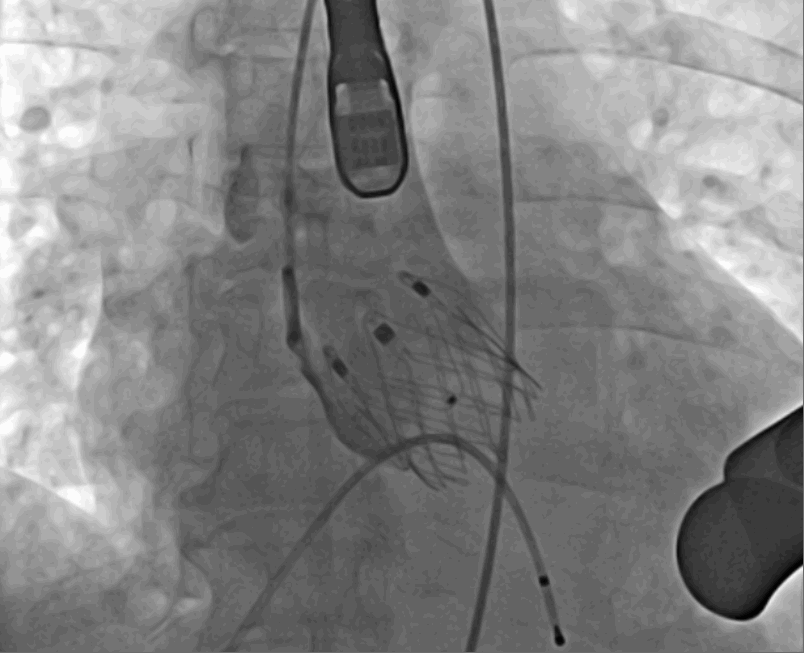

術(shù)前DSA影像圖

術(shù)中釋放定位鍵后DSA影像圖

術(shù)中瓣膜釋放過(guò)程

術(shù)后DSA影像